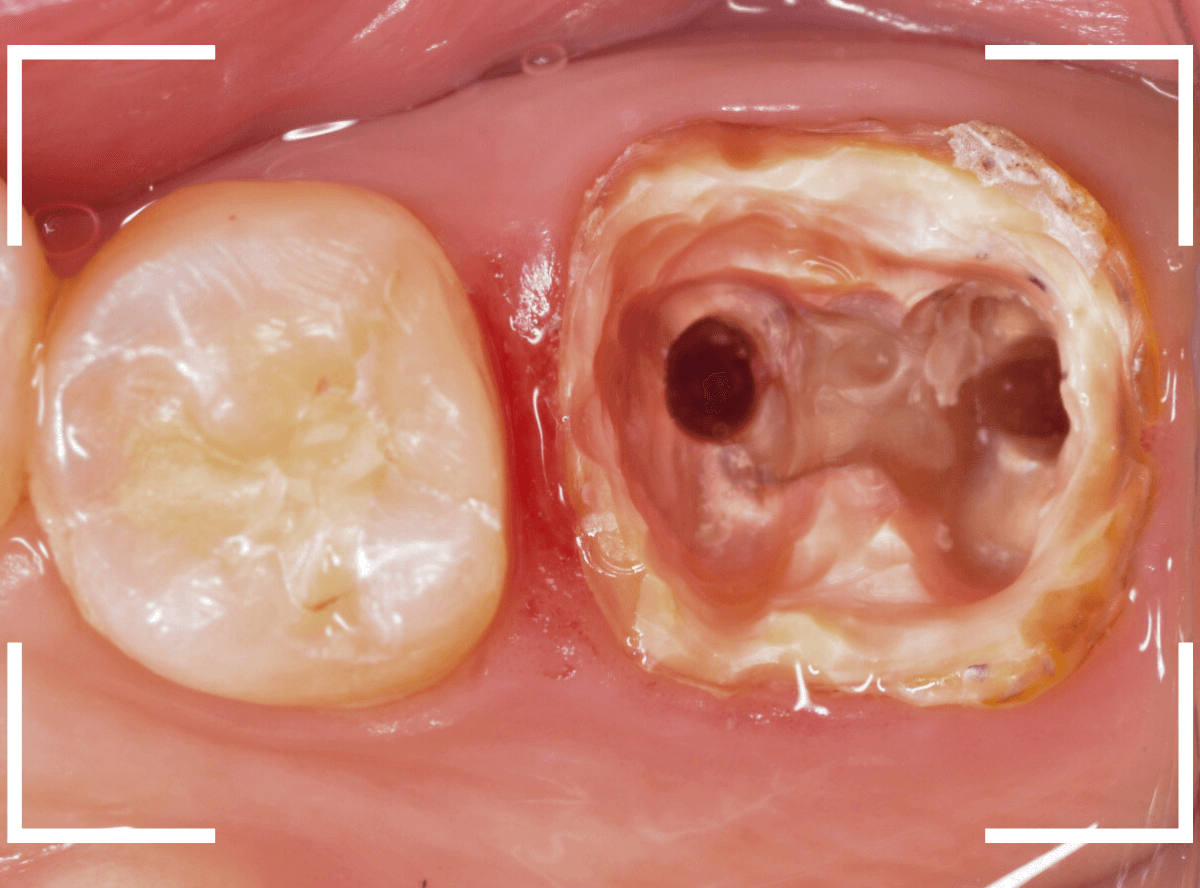

今回は、奥歯が神経に達する虫歯になってしまった患者さんのケースです。

隣りの歯とのすき間に大きな穴が空いているのが見えます。

金属のつめものの下が、神経まで達する大きな虫歯になっています。

手前の歯の虫歯も金属の中まで虫歯になっていました。

手前の歯の虫歯もかなり広い虫歯でした。